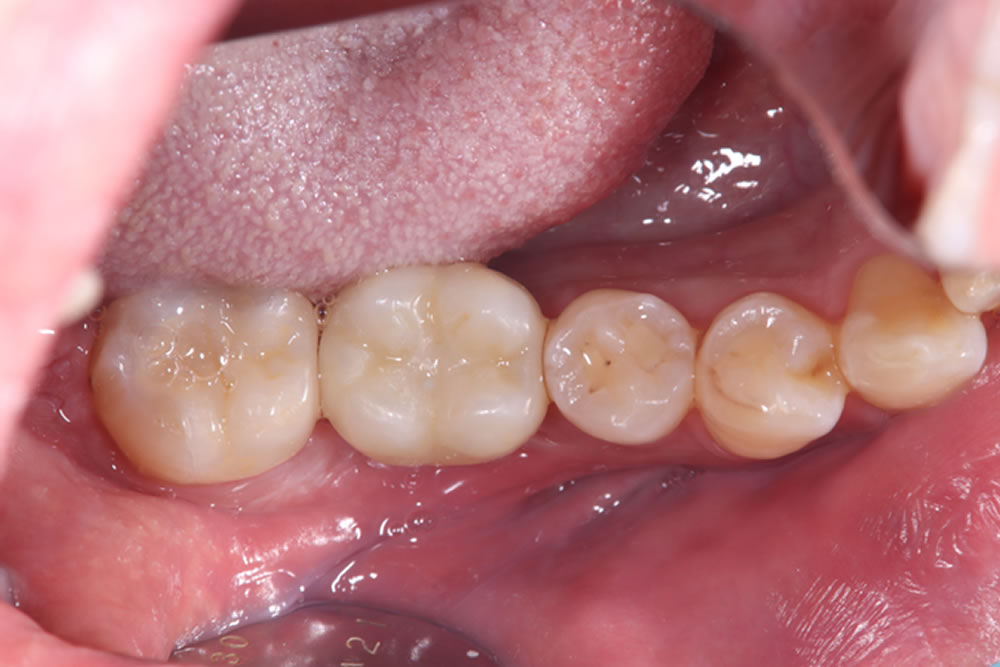

3ヶ月後に二次オペを行い、その後の歯肉の状態を確認したところ、周囲歯肉に炎症は認められませんでした。

また、奥の銀歯についてもセラミックへの置き換えを希望されていたため、同時につめ物の作成を行いました。

治療前後の比較

奥歯の痛みも消失し、快適に噛めるようになったとのことでした。また、最終的にはメタルフリーな口腔内となり、カリエスリスクの低減、審美性が向上しました。